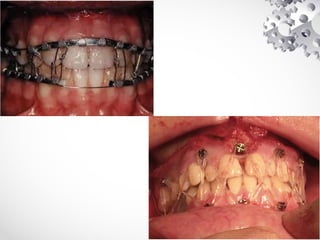

INTERMAXILLARY FIXATION (IMF)

• Can be used when the # is at a lower level (Le fort 1) and not grossly

displaced

• Done by wiring the teeth together (using teeth as biological bone pins) -

dental wires, arch bars, leonard button

• Advantage - Easy technique

• Disadvantage - Period of immobilization was inconveniet &

uncomfortable

- Dietary restrictions

- Fixation is often inadequate esp if dentition is incomplete

- Needle stick injuries to doctor and nursing staff

FRACTURE OF ANGLE

Closed Reduction

• Done by intermaxillary fixation (IMF)

• Limited role in modern maxillofacial surgery

• Has still a part to play in

(1) pts with undisplaced fracture & no neural deficits who don't want

surgery

(2) pts with unicondylar fracture

• Intact dental arch - Dental tie wire

• Incomplete arch - Arch bars, Intermaxillary bone pins, Cast silver splints

• Edentulous pts - Gunning splints